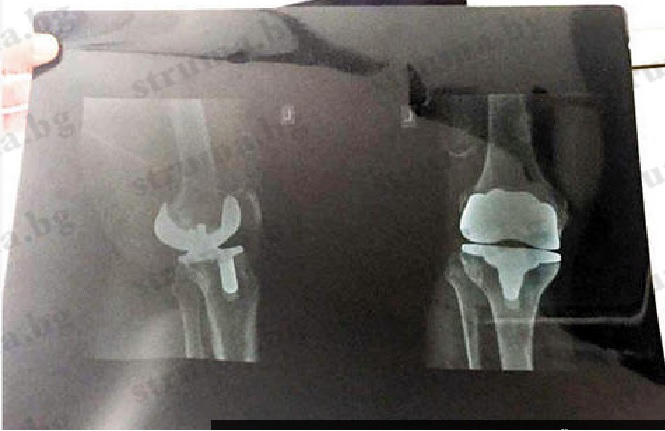

Операция, провеждана за първи път у нас, претърпя президентът на ОФК "Беласица" д-р Мазнейков. Международен екип от специалисти, воден от немския д-р Потрет, включващ и гръцкия хирург Папагеоргиу, подмениха лявата колянна става на петричанина със заместител уникат, съобщи "struma.bg". Изкуствената става е произведена в Щатите съобразно персоналните параметри на коляното на д-р Мазнейков и е моделирана на база снимките от скенер.